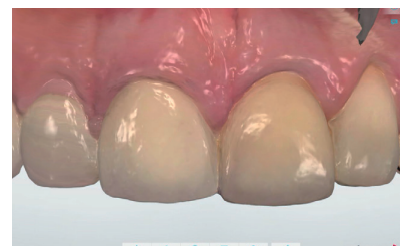

Utilizando el escáner 3Shape®, se realizó un pre-escaneado intraoral, primero con la corona dentosoportada colocada, para obtener la anatomía del incisivo central, y después sin ésta, escaneando así el perfil de emergencia del resto radicular; se informó al laboratorio de la modificación del perfil critico, corrigiendo así la recesión existente respecto al 1.1 (Figuras 5-7). Este escaneado sirvió a su vez para la toma de color del futuro provisional7,8. El archivo STL fue enviado al laboratorio protésico para elaborar la prótesis provisional tipo Maryland, en polimetil-metacrilato (PMMA), con dos apoyos en los bordes incisales de los dientes adyacentes para asegurar su correcto posicionamiento que, según la planificación previa, serviría como diente provisional, así como de guía quirúrgica para la inserción del IOI en la posición protésica idónea, evitando así posibles problemas futuros a nivel protésico o en la integridad de los tejidos blandos y duros de la región vestibular (Figuras 8 y 9).

Tras conseguir un volumen de tejido óptimo mediante el manejo del provisional (Figura 17), se realizó un primer escaneado del maxilar con la corona provisional atornillada para obtener la anatomía (Figura 18) y, posteriormente, un segundo escaneado sin la misma, registrando de forma precisa los contornos gingivales y el perfil de emergencia conseguido (Figura 19), así como la posición del implante mediante el scan body (Figuras 20 y 21). Para un correcto duplicado del perfil de emergencia, se procedió a escanear la corona provisional fuera de la boca (Figuras 22 y 23), evitando tener que realizar la técnica clásica de un transfer individualizado17. Estos registros fueron enviados al laboratorio protésico, el cual diseñó una estructura metálica sinterizada postmecanizada (Figura 24). Una vez realizada de forma satisfactoria la prueba de la estructura (Figura 25), se tomó el color de la restauración (A2 guía VITA) mediante un filtro de luz polarizada (Figura 26). Estos registros se enviaron de nuevo al laboratorio protésico para la finalización de la corona implantorretenida sobre los modelos impresos (Figuras 27 y 28). Previo a la colocación de la corona definitiva, se comparó el perfil de emergencia de la corona provisional con la definitiva, viendo la similitud entre ellas (Figura 29), consiguiendo así preservar los perfiles mantenidos desde el día de inicio del tratamiento.